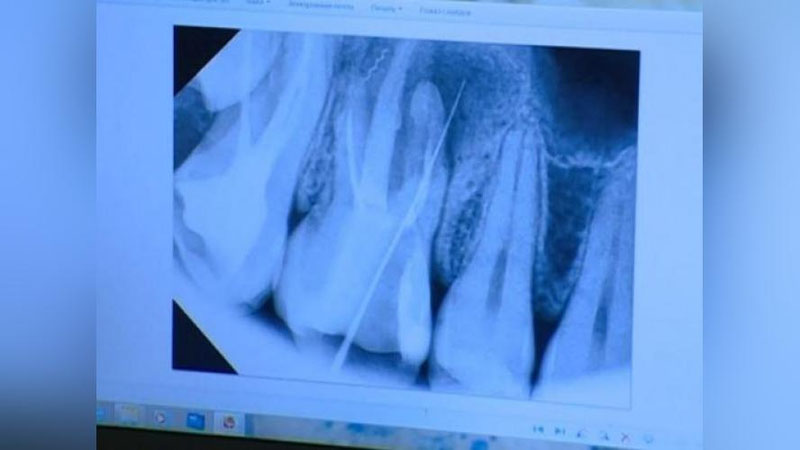

В конце концов, когда она пришла на прием в другую клинику, врач сообщил, что зуб разрушился, и его остается только удалить. После удаления специалист показал пациентке оставшийся в зубе обломок иглы и посоветовал обратиться в правоохранительные органы. Однако С. Сапаева отказалась это делать. Тогда хирург сам обратился в компетентные органы, представил амбулаторное заключение и попросил принять меры. В отношении Д. Сабирова было возбуждено уголовное дело. Приговором суда лжеврач получил соответствующее наказание.